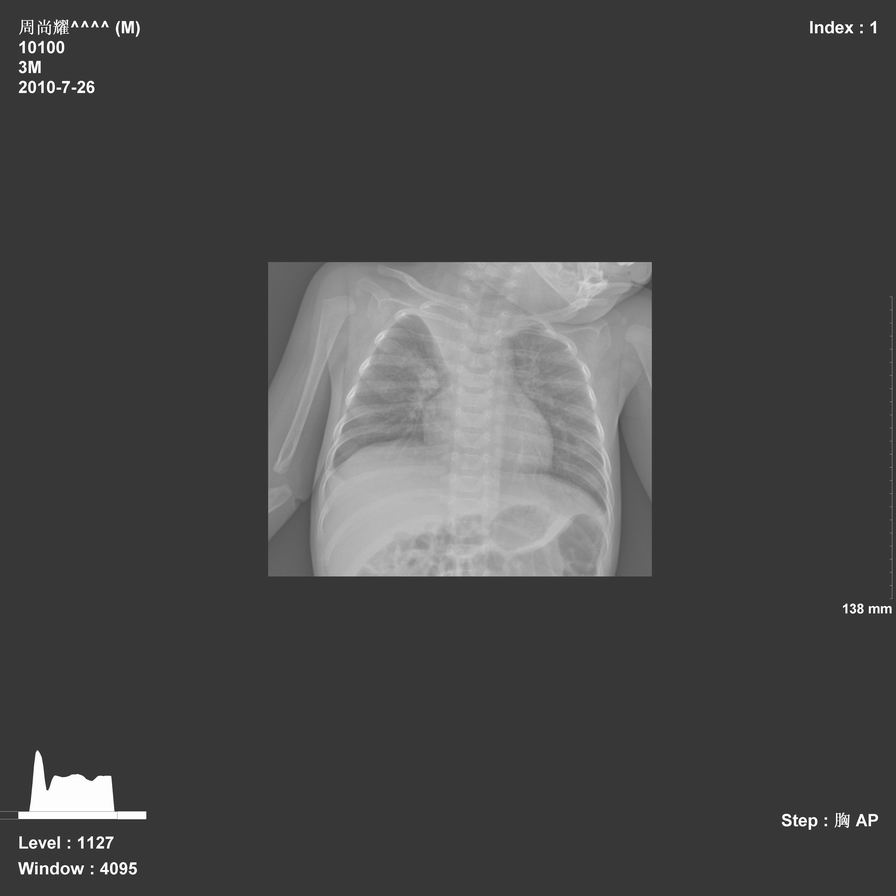

以下是引用jsdtd在2010-7-26 14:42:00的发言:[br]胸腺呈帆状,体位所致,没事。

以下是引用aa13877358820在2010-7-26 12:35:00的发言:[br]男性,三个月,卧位胸片,咳嗽、气促、发热14天,两肺闻及细小水泡音。[br]